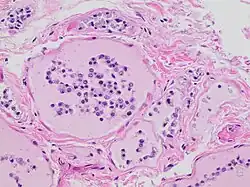

Autolysis is uncommon in living adult organisms and usually occurs in necrotic tissue as enzymes act on components of the cell that would not normally serve as substrates. These enzymes are released due to the cessation of active processes in the cell that provide substrates in healthy, living tissue; autolysis in itself is not an active process. In other words, though autolysis resembles the active process of digestion of nutrients by live cells, the dead cells are not actively digesting themselves as is often claimed, and as the synonym self-digestion suggests. Failure of respiration and subsequent failure of oxidative phosphorylation is the trigger of the autolytic process.[1] The reduced availability and subsequent absence of high-energy molecules that are required to maintain the integrity of the cell and maintain homeostasis causes significant changes in the biochemical operation of the cell.

Limited synthesis of adenosine triphosphate impairs many cellular transport mechanisms that utilize ATP to drive energetically unfavorable processes that transport ions and molecules across the cellular membrane. For example, the membrane potential of the cell is maintained by the sodium-potassium ATPase pump. Failure of the pump results in loss of membrane potential as sodium ions accumulate within the cell and potassium ions are lost through ion channels. Loss of membrane potential encourages movement of calcium ions into the cell, followed by movement of water into the cell, as driven by osmotic pressure.[3] Water retention, ionic changes, and acidification of the cell damages membrane-bound intracellular structures including the lysosome and peroxisome.[1]

Lysosomes are membrane-bound organelles that typically contain a broad spectrum of enzymes capable of hydrolytic deconstruction of polysaccharides, proteins, nucleic acids, lipids, phosphoric acyl esters, and sulfates. This process requires compartmentalization and segregation of enzymes and substrates via a single intracellular membrane that prevents unwarranted destruction of other intracellular components. Under normal conditions, the molecular machinery of the cell is further protected from lysosomal enzyme activity by regulation of cytosolic pH. The activity of lysosomal hydrolases is optimal at a moderately acidic pH of 5, which is significantly more acidic than the more basic average pH of 7.2 in the surrounding cytosol.[1] However, the accumulation of products of glycolysis decreases the pH of the cell, reducing this protective effect. Furthermore, lysosomal membranes damaged by water retention in the cell will release lysosomal enzymes into the cytosol. These enzymes are likely to be active due to the decreased cytosolic pH and are thus free to utilize cellular components as substrates.[1]